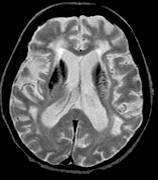

3. With regard this physical sign:

e. a brain MRI scan may of this patient may show the picture below